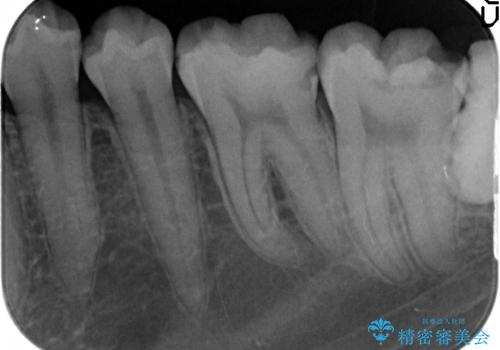

左下7の虫歯は深く、また歯冠高径も低かったため、歯冠長延長術を行いました。

歯茎より深い虫歯治療について

虫歯が進み歯茎より深くなってしまうと、虫歯を取り残してしまうリスク、樹脂の硬化の妨げ、補綴物の不適合、歯肉炎・歯周病のリスクの増大等様々な弊害が起こり得ます。